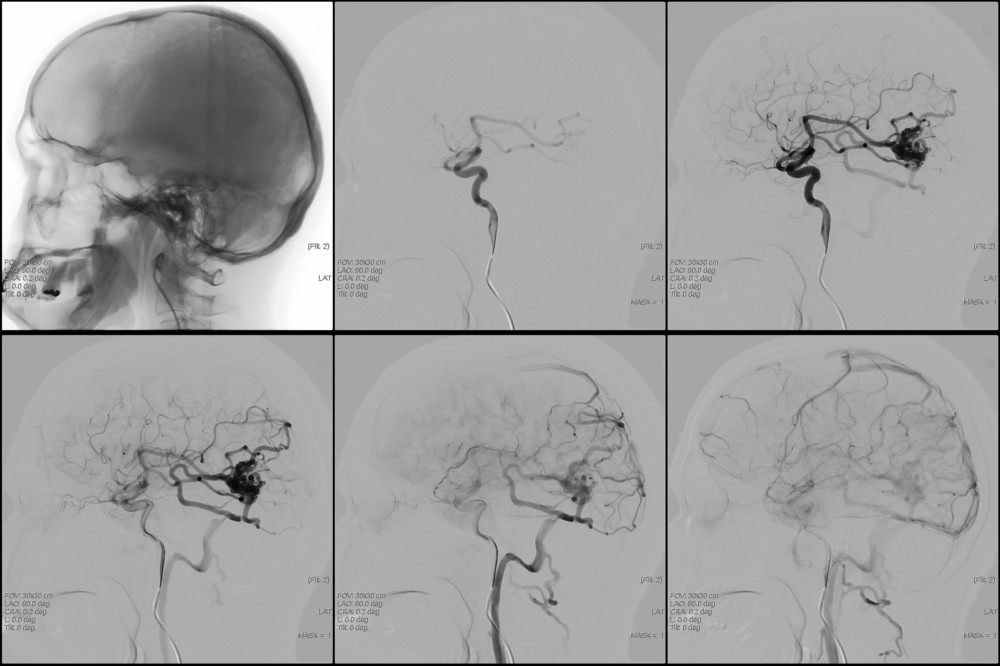

Поражения сосудов головного мозга

Не менее распространённым заболеванием сосудов головного мозга является ишемическая болезнь головного мозга. Это неврологическое заболевание возникает в результате изменения сосудисто-церебрального кровообращения из-за сужения или закупорки мозговых сосудов, что приводит к негативным изменениям головного мозга. Появляются головные боли, внезапные головокружения, нарушения речи, нечёткость зрения, иногда приводящее к слепоте. Могут отмечаться и двигательные нарушения-слабость в конечностях, паралич. Нередко возникает ишемический инсульт.

Чаще всего ишемическая болезнь головного мозга развивается в результате атеросклероза, травмы головы и шеи, повышенного внутричерепного давления, врождённых сосудистых аномалий.